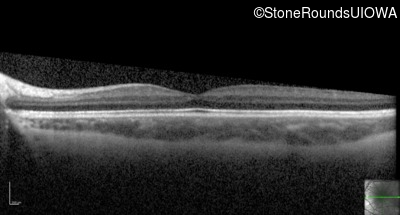

Optical Coherence Tomography - Right - 20/50

Exemplar / OCT Stack